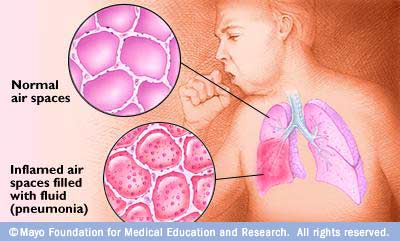

التهاب الرئة هو عبارة عن التهاب في الحويصلات الرئوية، التي تمتليء بسائل صديدي، وبذلك يجد الاكسجين صعوبة في الانتقال من الحويصلات إلى الأوعية الدموية، وإذا قلت نسبة الاكسجين في الدم فإن الخلايا لا تستطيع أداء عملها على الوجه المطلوب.

يصيب الالتهاب فصآ كامآ أو جزءآ منه أو أجزاء متفرقة من فصوص مختلفة، وتمتلتيء الحويصلات بالسوائل الالتهابية والصديد، ويمكن أن ينتقل الالتهاب إلى الدم مسببآ ما يسمى (Bacteremia) أو إلى السحايا مسببآ التهاب السحايا (Menengitis)

الالتهاب الرئوي الفيروسي:

يمثل التهاب الرئة الفيروسي حوالي نصف حالات إلتهاب الرئة

تزيد عدد الفيروسات المسببة للالتهابات التنفسية مع مرور الايام والسنين، وعلى الرغم من أن أكثرها تسبب التهاب الجهاز التنفسي العلوية إلا أن بعضها يسبب الالتهاب الرئوي خصوصآ في الطفال، لكن الاصابة عادة تكون بسيطة ويتماثل المصاب للشفاء من تلقاء نفسه، لكن في بعض الاحيان يمكن أن تكون الاصابة خطيرة وأحيانآ قاتلة وخاصة في المصابين بأمراض القلب أو الرئة أو السيدات الحوامل.